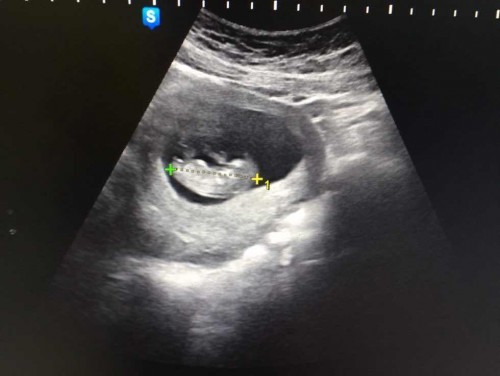

แม่ๆคะเราท้องเเรกคะ คือเราตอนนี้13week ขออนุญาตนะคะ เรามีเพศสัมพันธ์กับแฟนบ่อยคะตั้งเเต่ท้องเดือนเเรก เราพึ่งรู้ตัวว่าท้องตอน7weekคะ ที่นี้เราก็ลดน้อยลงนะคะ เเล้วมีวันนึงเเฟนเรามีอะไรกับเราเเรงมากค่ะเเรงจนเราบอกให้หยุดเรากลัวลูกเป็นอะไรไปหลังจากนั้นเราก็กังวลเรื่อยมาเลยคะ ท้องเราก็ไม่ออกปวดท้องบ่อยเราถามคนเคยมีลูกเขาบอก13weekก็เริ่มตอดเเล้วเเต่เราไม่รู้สึกอะไรเลย จับหน้าท้องก็ไม่เห็นมีเสียงหัวใจเต้น เราพยายามจิ้มท้องให้รู้สึกว่าเขาตอดเเต่ก็ไม่เลยคะอีกอย่างเราฝากธรรมดาคะ หมอไม่บอกอะไรเลยภาพนี้ซาวด์ตอน11week5วันกังวลคะเเม่เรากลัวลูกหลุดมากหลังจากนั้นเราก็ไม่กล้ามีอะไรกับเขาอีกเลย#ขอบคุณล่วงหน้านะคะ #ท้องแรกคะ #ใครมีประสบการณ์